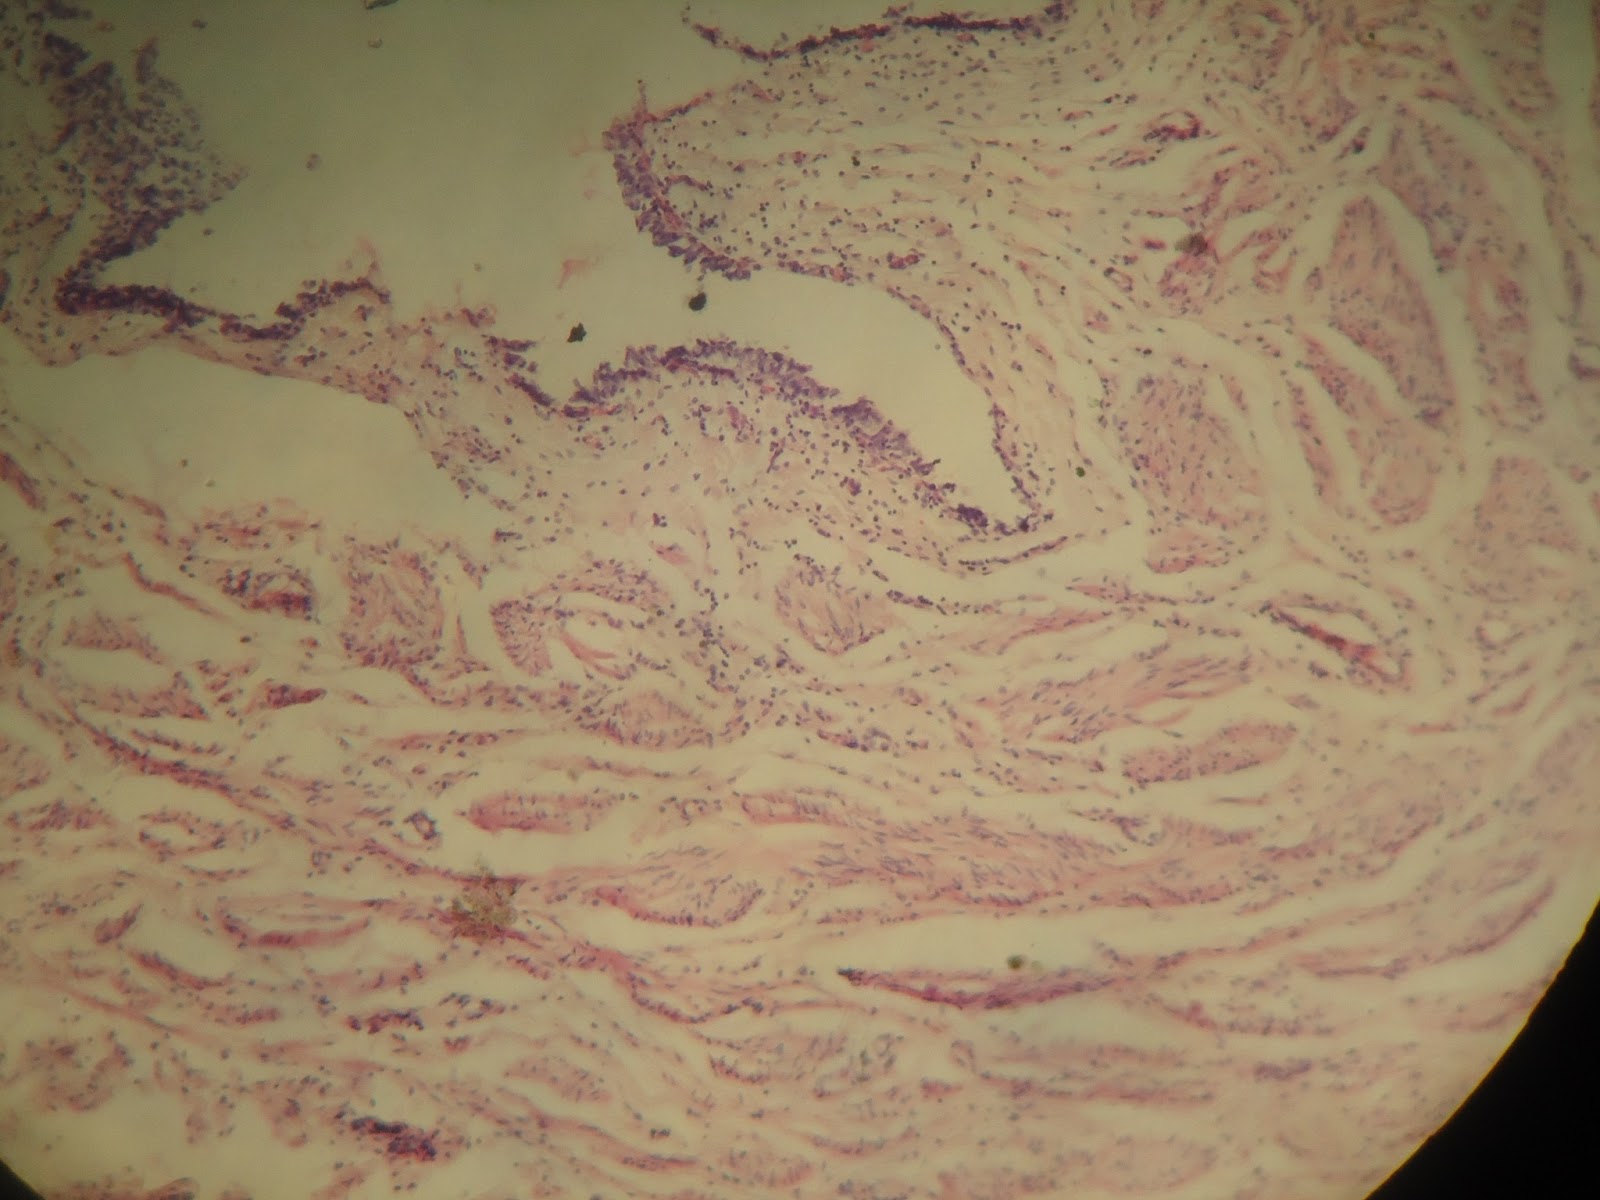

Se

distinguen fácilmente de los vasos sanguíneos porque presentan una pared muy

delgada y una luz de mayor diámetro. Se distinguen 3 tipos de vasos linfáticos:

los capilares, los vasos linfáticos propiamente tales y los gruesos troncos o conductos

mayores.

Vasos linfáticos pequeños:

Los capilares linfáticos confluyen hacia

los vasos linfáticos pequeños de lumen muy amplio y paredes finas, llamados también vasos

colectores. La pared de estos vasos posee por fuera del endotelio un refuerzo

de tejido conjuntivo con finos manojos colágenos, fibras elásticas,

fibroblastos y ocasionales fibras musculares lisas. Estos vasos linfáticos presentan

abundantes válvulas formadas por repliegues del endotelio con un fino esqueleto

interior de tejido conjuntivo. Estas válvulas se proyectan en el interior de la

luz del vaso, en el sentido de la corriente linfática y controlan la dirección

del flujo. En los vasos linfáticos de un tamaño mayor se pueden reconocer las 3

capas: intima, media y adventicia. La intima está compuesta de endotelio, y un

subendotelio de tejido conectivo con finas fibras elásticas longitudinales. La

media tiene una o dos capas de fibras musculares lisas circulares con finas y

escasas fibras elásticas entre ellas. La adventicia, que es la capa más gruesa,

está constituida por tejido conjuntivo con fibras colágenas longitudinales, y

entre ellas fibras musculares lisas longitudinales y fibras elásticas.